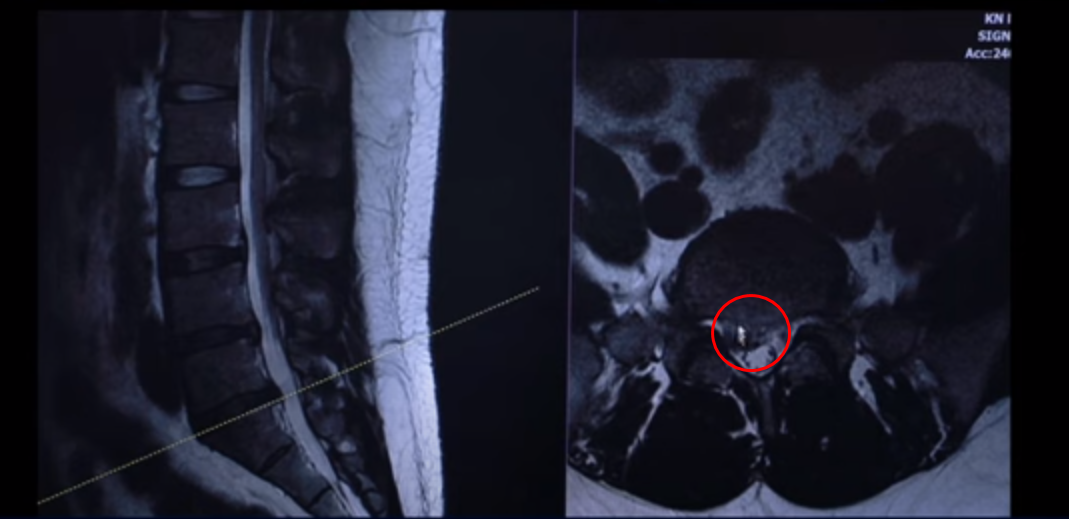

디스크 파열 30세 남자 환자분 MRI 보시겠습니다. 보시다시피 세 마디의 퇴행성 디스크가 있습니다.

5번 1번 마디가 가장 심하고요, 파열이 굉장히 심합니다. 그 다음에 4번 5번에도 디스크 탈출이 있습니다. 상당히 많이 튀어나와 있죠. 이를 돌출이라고 하는데 왼쪽으로 살짝 튀어나와 있죠. 이 정도면 증상을 일으킬 수도 있는데 이 환자분은 오른쪽 다리 증상입니다. 여기 보시면 오른쪽으로 밀려 나와 있습니다. 이게 환자의 오른쪽입니다.

이거는 색깔이 옅은 걸로 봐서 최근에 터진 디스크로 보입니다.

아무튼 이 환자분 5번 1번 디스크는 이렇게 보시다시피 심하게 튀어나왔고 이게 오른쪽으로 치우쳐져 있습니다.